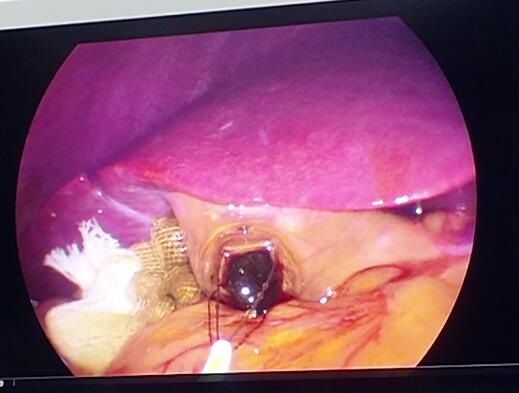

手术非常顺利,张智勇副主任通过脐部一个隐蔽的小切口,成功为彭女士取出了一颗黄褐色结石,大小约0.8×1.0厘米。术后,彭女士疼痛感很轻,当天就能下床活动,恢复速度也远超她的预期。

通过在患者肚脐处穿刺三个小孔共建立微通道进入胆囊,自动建腔显露术野,完成手术。